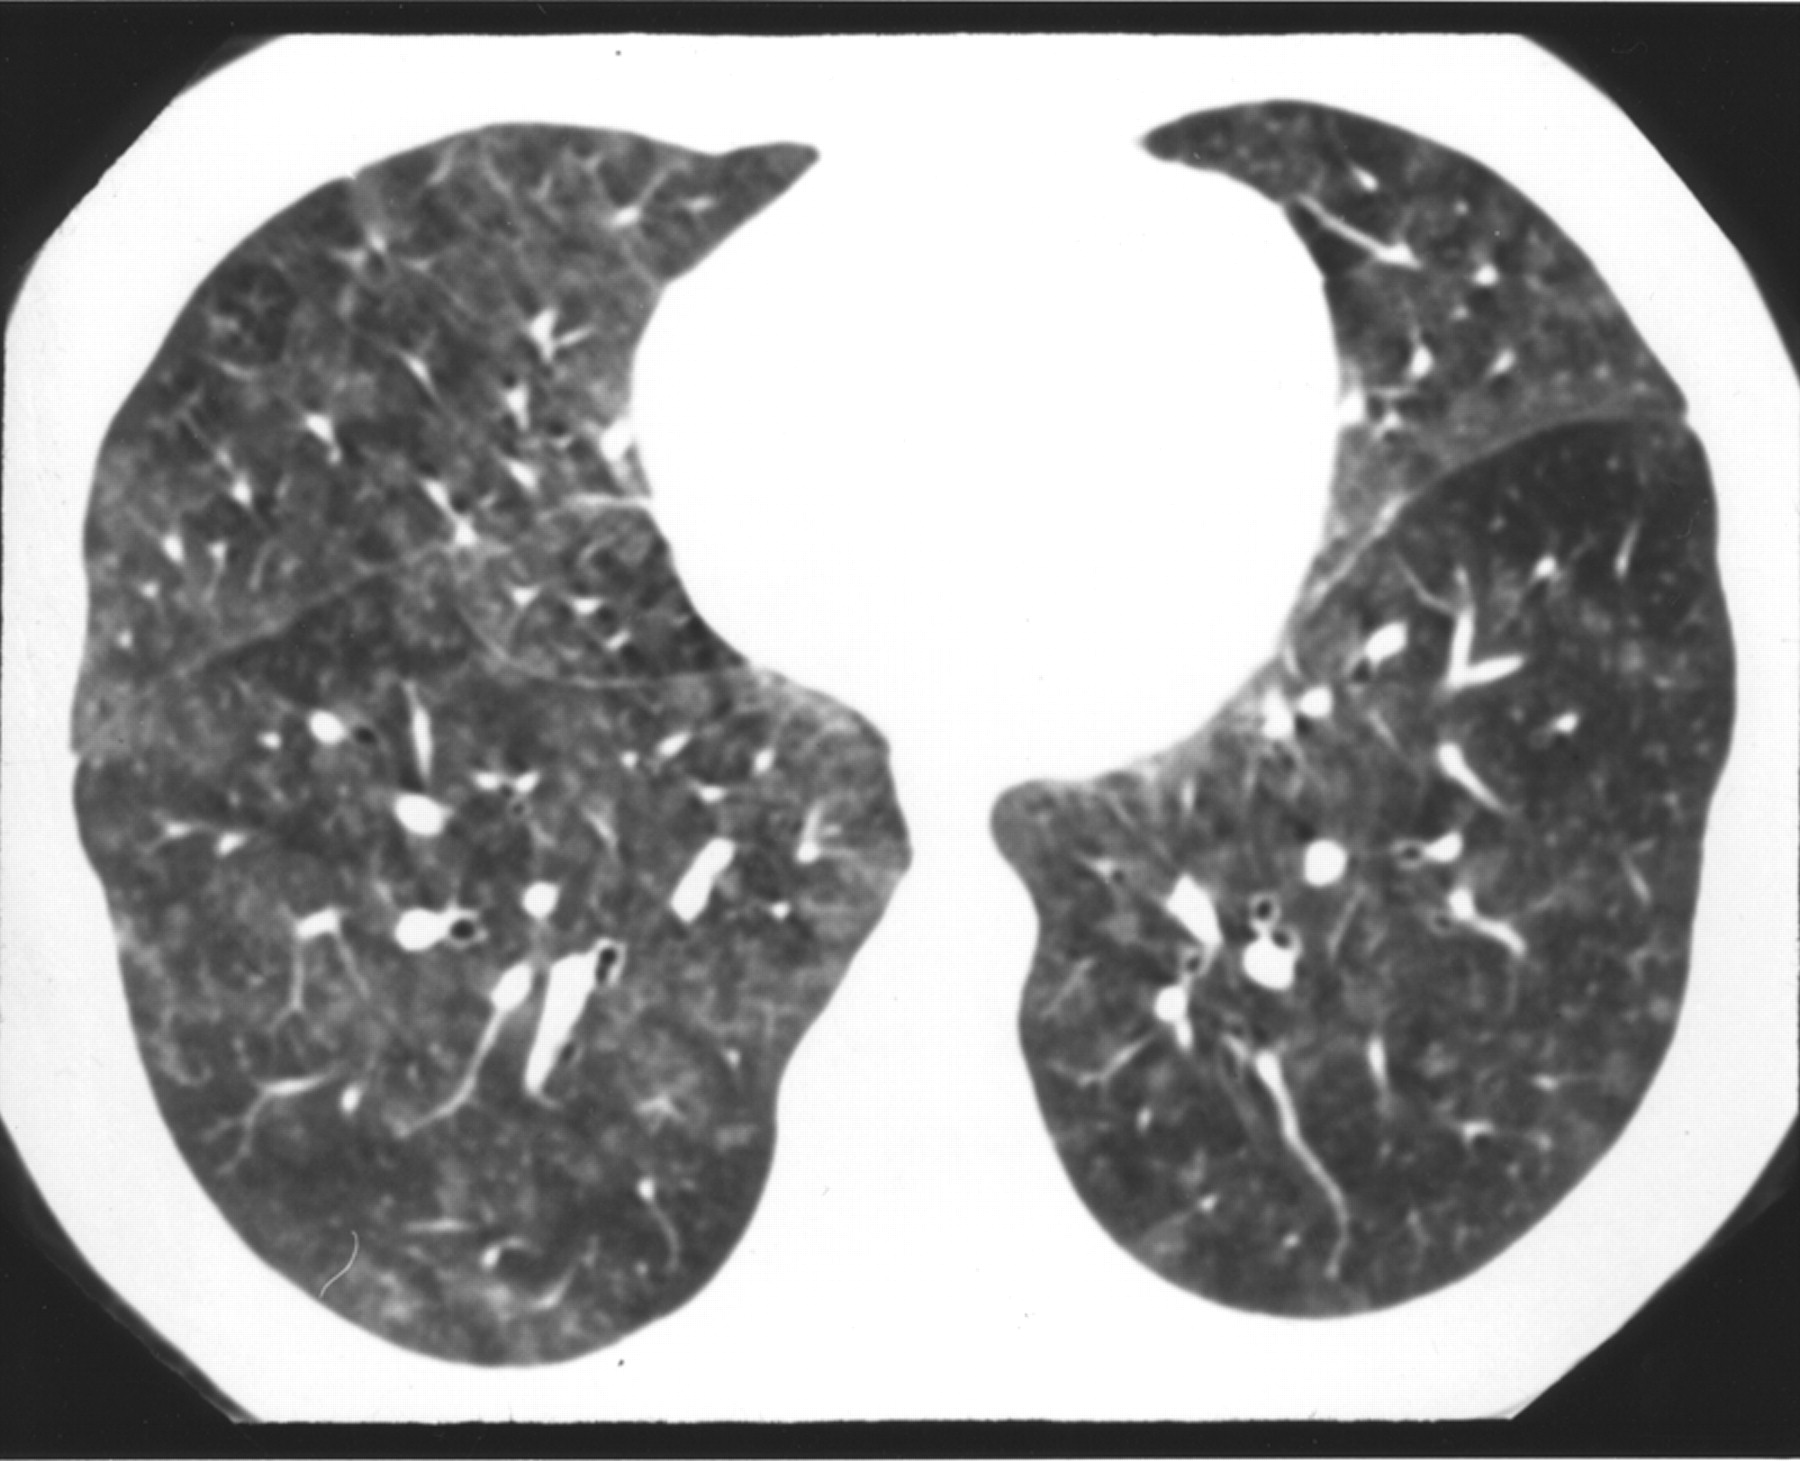

Head Cheese Hypersensitivity Pneumonitis . Hypersensitivity pneumonitis (hp) classified as an interstitial lung disease is characterized by a complex. Red arrows indicate hyperinflated lobules, red stars indicate.

Red arrows indicate hyperinflated lobules, red stars indicate. Hypersensitivity pneumonitis (hp) classified as an interstitial lung disease is characterized by a complex.

The 'headcheese sign' in chronic hypersensitivity pneumonitis.... Download Scientific Diagram Head Cheese Hypersensitivity Pneumonitis Red arrows indicate hyperinflated lobules, red stars indicate. Hypersensitivity pneumonitis (hp) classified as an interstitial lung disease is characterized by a complex. Head Cheese Hypersensitivity Pneumonitis.